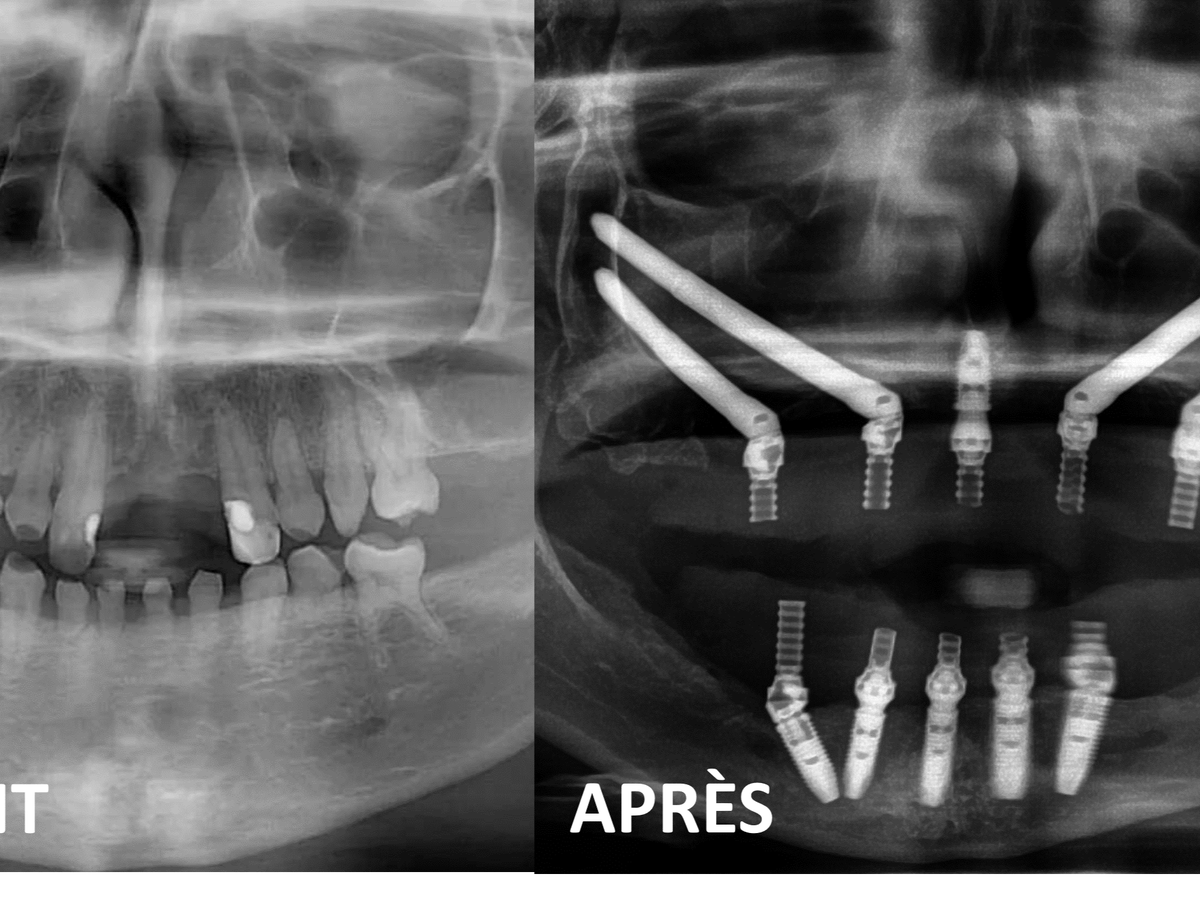

Suite aux visites de soumissions chez deux intervenants spécialistes, j’apprends que c’est un montant de 70 350 $ qui sera nécessaire afin de reconstruire ma dentition au Québec. Un chirurgien maxillo-facial s’occuperait des extractions et implants pour mes deux mâchoires. Son coéquipier, dentiste spécialisé en prosthodontie, se chargerait des prothèses permanentes et temporaires utiles durant la guérison des implants qui prendra 6 mois à 1 an. J’ai besoin d’aide pour payer ces frais énormes.

After the visits to two specialist providers, I learned that an amount of $70,350 will be needed to reconstruct my teeth in Quebec. A maxillofacial surgeon would take care of extractions and implants for both of my jaws. His teammate, a dentist specializing in prosthodontics, would take care of the permanent and temporary prostheses useful during the healing of the implants, which will take 6 months to 1 year. I need help to pay these huge fees.